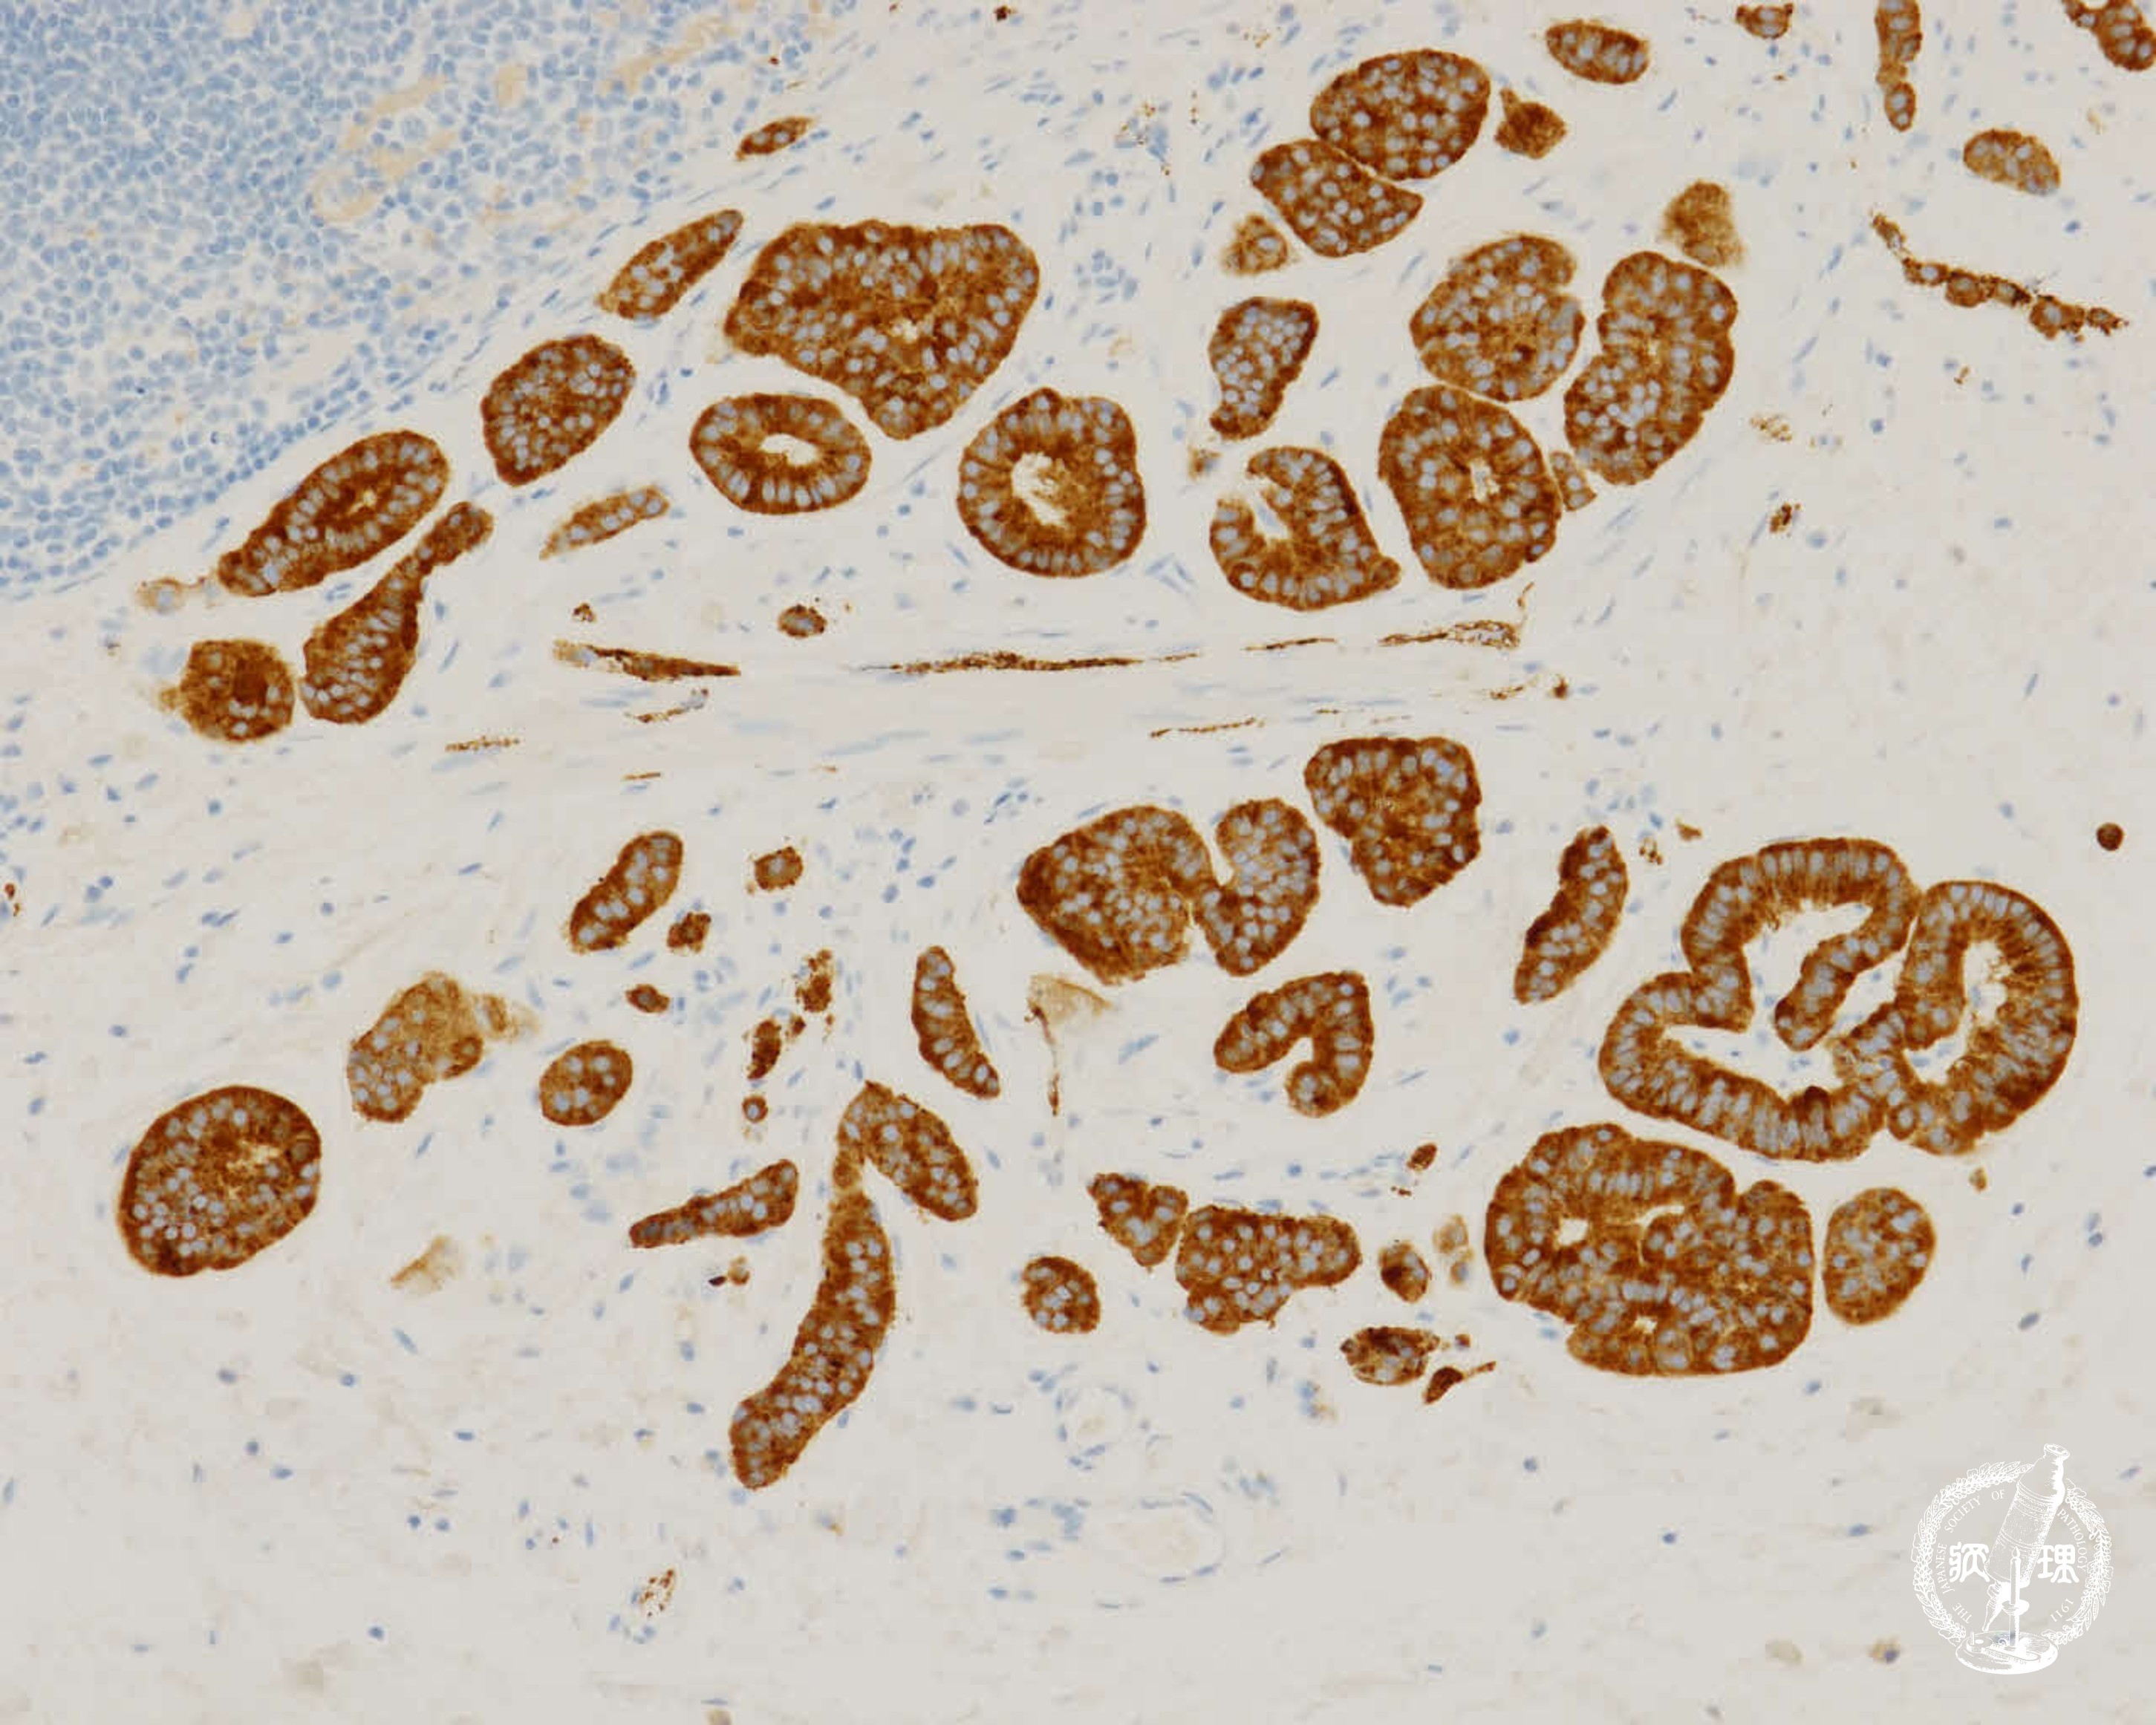

(10)大腸カルチノイド腫瘍

ミクロ像(HE弱拡大):直腸の粘膜下層に異型腺管の増生を認める(矢印)。